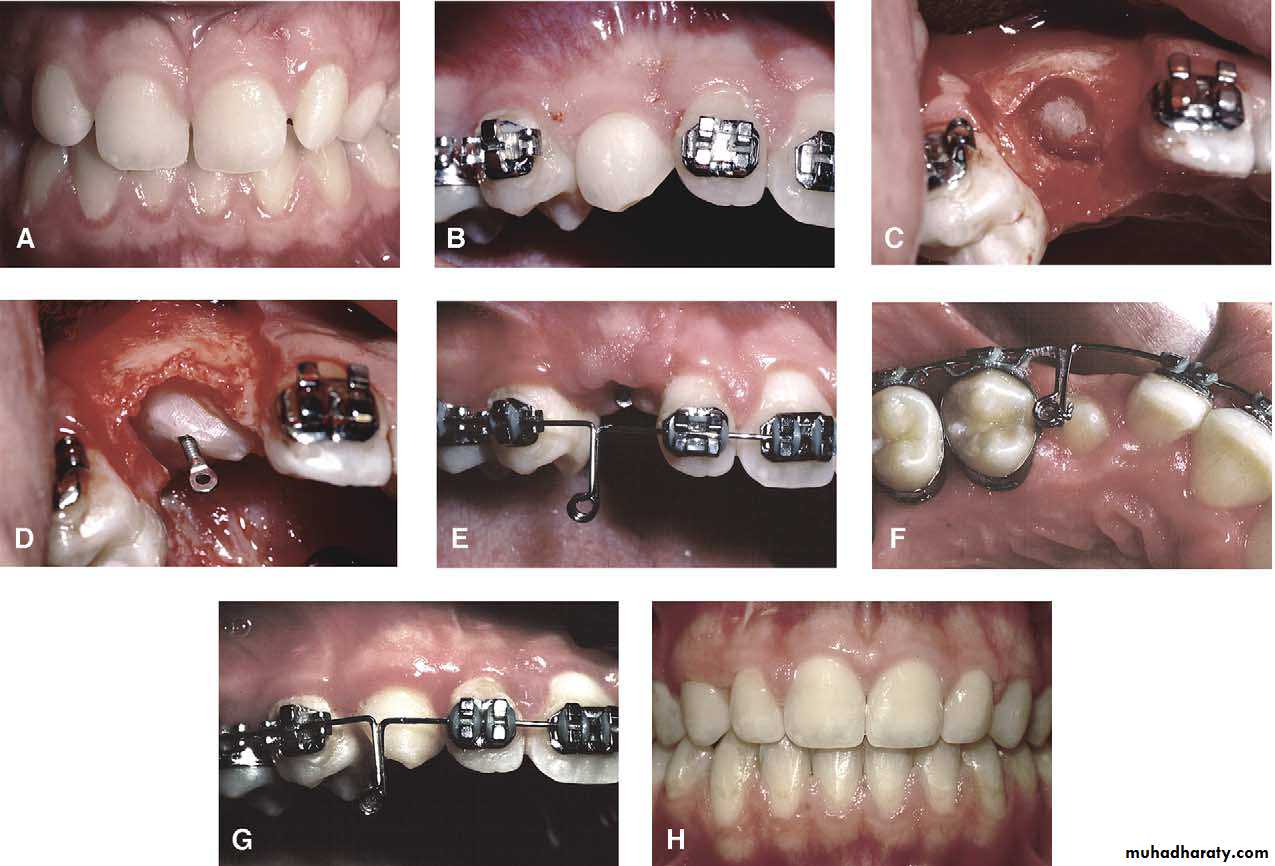

Surgical exposure

An attempt is made to assist the eruption of a malposed and unerupted canine into a functional position . It is considered when :1- there is adequate room in the arch to accommodate the tooth .

2- the potential path of eruption is unobstructed

3- exposure of the crown can be carried out as close as possible to the time at which normal eruption would occur .

Mosul university- College of dentistry-oral & maxillofacial surgery department

The initial stage of the operation is to reflect the mucoperiosteum and to remove the bone overlying the tooth to expose the greatest coronal diameter, the incisal edge and the cingulum . before repositioning the palatal flap a window is excised in it corresponding to the bony cavity containing the crown .the flap is then sutured as usual and a pack of iodoform gauze should be pressed firmly in to the bony defect so as to cover the exposed crown .

This pack should be held in position with suture and left insitu for 2-3 weeks to prevent granulation tissue and mucosa from overgrowing the denuded crown .after removal of the pack the progress of eruption should be observed at frequent intervals .

Following eruption of the tooth , orthodontic treatment may be required to guide it into a good position in the arch . Some times orthodontic traction is arranged at the time of surgery .

Surgical exposure :the path of eruption is not obstructed

Surgical exposure with orthodontic treatment : the path of eruption is obstructed

Surgical exposure with orthodontic treatment (palatal approach )